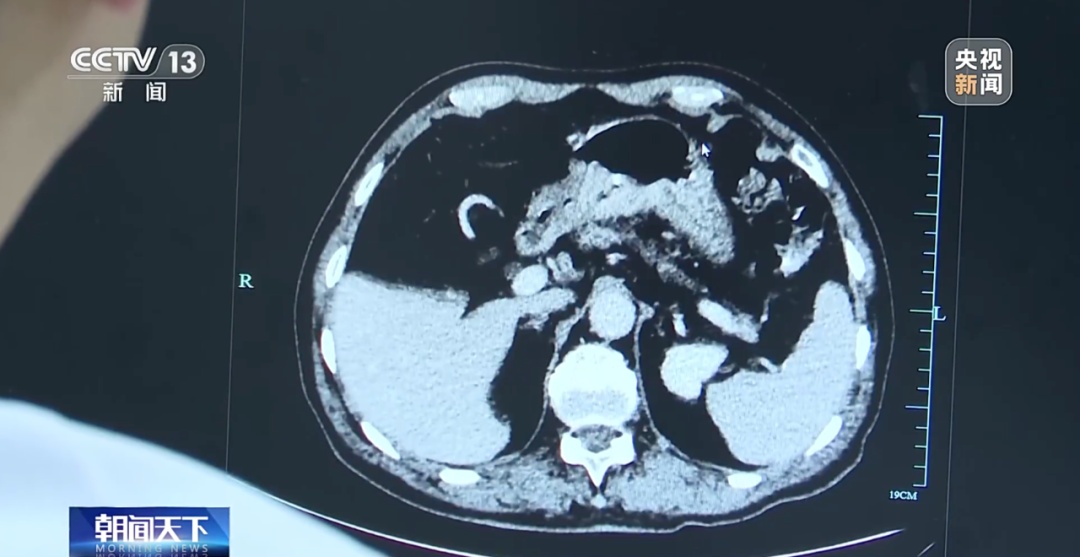

近期,浙江大学医学院附属第一医院胃肠外科接诊了一位18岁患者。这名患者罹患低分化腺癌,这是一种易复发、易转移的恶性肿瘤疾病。

医生介绍,这位患者通常每周吃三顿烧烤,还长期吃腌制食品和熏烤食品,导致胃癌发病率增加。患者在微创手术中切除了三分之二的胃,目前已经出院。